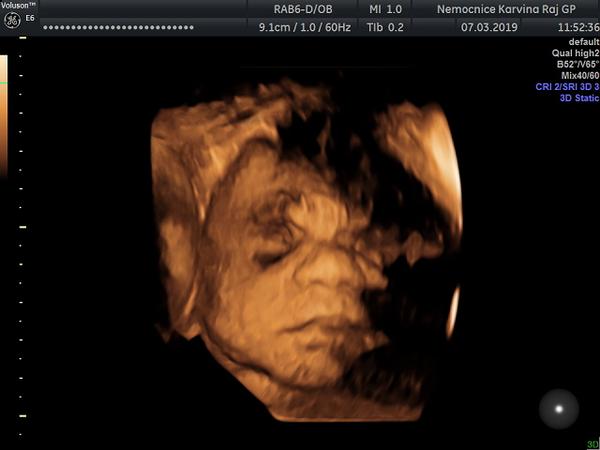

3D ultrazvuk - stojí to za to?

Stojí to za to? 🙂 Jaký jsou pak fotky? Dívala jsme se s manželem na google, jak ty fotky vypadají. A ani mě ani manželovi se ty fotky vůbec, ale vůbec nelíbí :D :-/

Nechci to nijak znevažovat, pomlouvat, rozmlouvat. To určitě ne 🙂 Miminko nám na fotkách přijde takový neforemný, nehezký. Naše miminko už teď milujeme 🙂

Věřím, že to je hezká vzpomínka na těhotenství. Změní se nám názor, až miminko na 3D uvidíme? Opravdu to stojí za to? 🙂

Dnes jsem se doktora ptala na ten 3D utz. Dělá ho on, stojí to 1500 a je to strašně nejisté, může to být za 10 minut hotový nebo tam může hodinu lovit aspoň trochu přijatelný záběr :D Ještě to promyslíme 🙂